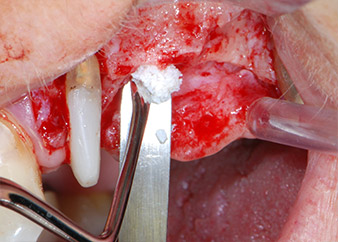

Prior to implant placement, and following verification of an intact Schneiderian membrane (Fig. 9), the internal sinus floor was augmented at both implant sites by means of xenogeneic bone substitute material (Bio-Oss, Geistlich Biomaterials) (Fig. 10).

The implants (Restore, Keystone Dental, diameter 3,75 mm, length 8.0 mm) were placed with the implant motor (Figs. 11 and 12).